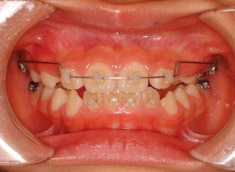

治療開始から3ヶ月後

治療開始して3ヶ月で前歯はジャンプしておりますが、フェイスマスクをこの後もしっかり使用していただくことが大切です。

まだ治ったわけではないのです。